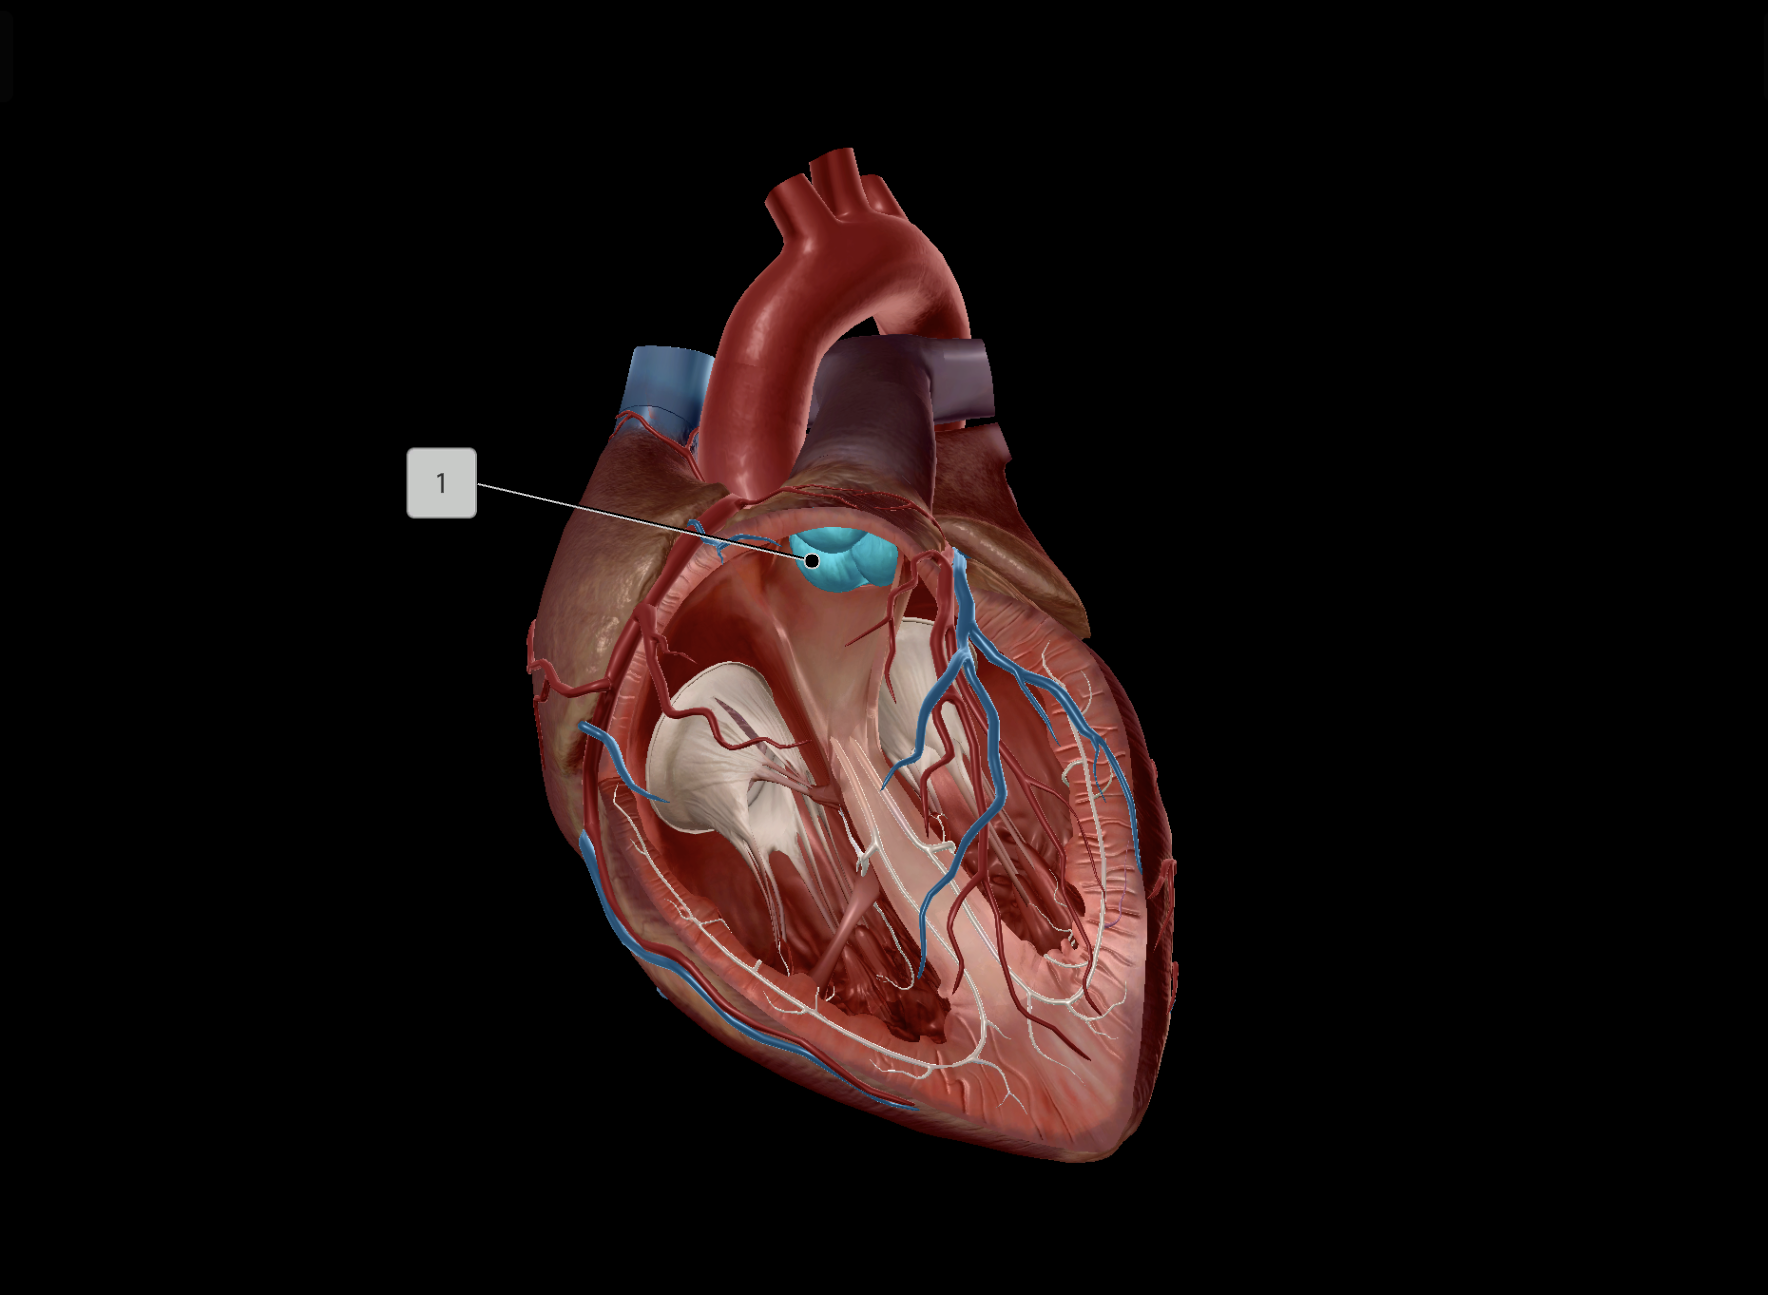

Tricuspid Valve

Bicuspid Valve

Aortic Valve

Papillary Muscle

Pulmonary Valve

Interventricular Septum

Chordae Tendineae

AV Node

SA Node

Bundle of His